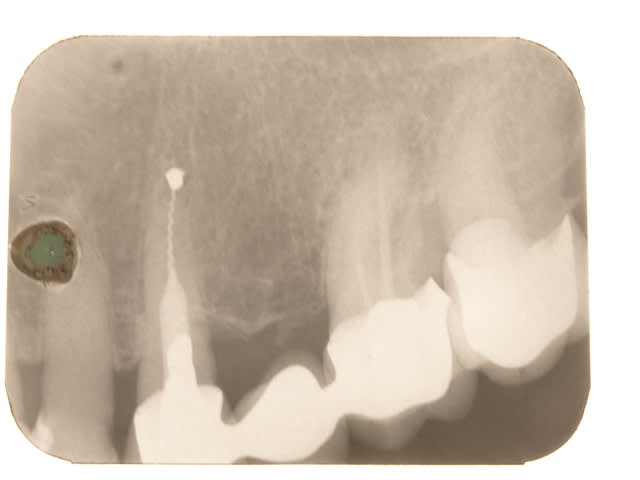

Euh .......les gas y a pas un truc qui vous gêne là ? Vous avez vu les radios ?

Premièrement il faudra que m'expliquer comment le bridge qui au départ est infiltré voir carié sur la 4 se retrouve comme par magie ré-adapté.

Le tenon n'est pas le même

Le traitement endo n'est pas le même

La 7 est couronnée (cantilever) sur une radio , pas sur la radio pré-op

Le niveau osseux n'est pas le meme sur les 2 radios

BREF IL NE S'AGIT PAS DU MEME PATIENT....

Tu dis avoir démonté le bridge et reposé tel quel , ce qui est faux au vu de la radio pré-op en page 5..... le tenon , ete le trt endo sont différents .

Tu as donc inventé une technique pour réadapter des prothèses non adaptées ....... le hyatus a disparu comme par magie , donc 2 possibilités :

- Tu as refait le bridge et tu ne le dis pas

- La radio pré-op est de quelqu'un d'autre

Les autres radios je m'en fous , je dis juste qu'entre les deux radios (15 ans) il y a du y avoir une intervention divine ....

Je te trouve bien hargneux sur ce bridge, parce que si tu regardes bien les radios tu vois bien que c'est le même patient quand-même, et que la 7 a été couronnées par la suite. Les radios ont une incidence un peu différente.

Si 15 ans sépare la radio pré opératoire de la dernière radio, force et de constater que la réimplantation a fonctionné.

Je note néanmoins une cratérisation apparue autour de la partie cervicale de la racine réimplanté, suite à l'intervention, mais stabilisée par la suite.